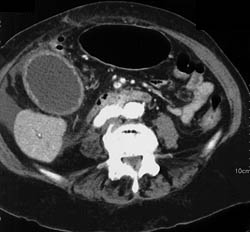

Focal Nodular Hyperplasia (FNH)